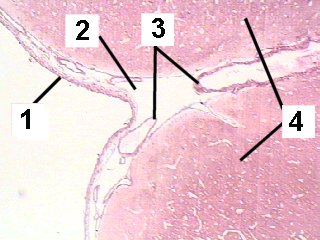

A low magnification of the brain demonstrating the meninges.

Fig 061-005 |